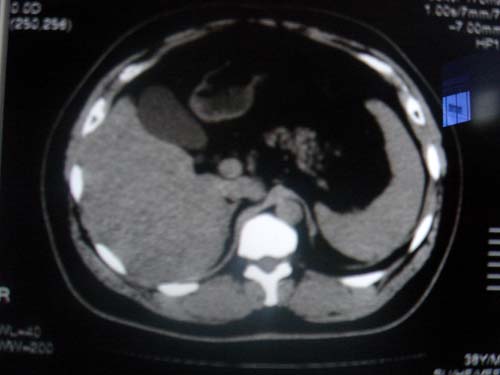

患者 男 40 右上腹不适 有胆囊息肉病史2年

本例就是胆囊比较大,内密度不很均匀,疑有砂砾状结石,未见息肉以及其他异常。

肝脏增大,

最后二副图像示胆囊壁增厚,与肝分界欠清,建议强化ct或磁共振

片中示肝脏的ct值低于脾脏,肝脏右叶外缘部份凹凸不平,考虑脂肪肝,肝硬化可能。结合其检查如b超或ct增强检查。

胆囊未见明显异常,肝脏密度似比脾脏密度低,测量一下ct值排除一下脂肪肝.当然做一下增强或mr就更好了.

肝右叶密度不均,脾大。强烈要求增强扫描除外浸润型肝癌。

肝大   密度降低  脾大  脂肪肝?